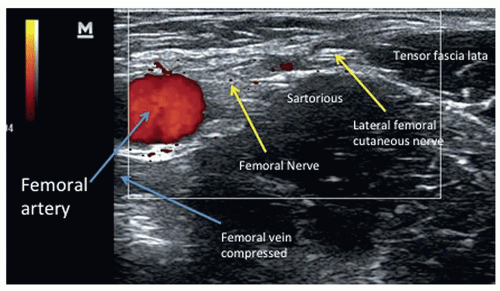

MP의 초음파 소견에는 LFCN 저음영화, 비정상적인 신경주위 경계, 신경내 혈관성, 신경 단면 확대, 그리고 전상장골극(ASIS) 근위부의 확산성 국소 비후가 포함된다. 12,13 유사한 병리학적 변화는 MRI 신경조영술을 통해 조사되었으며, LFCN의 지속적인 고신호 강도, 신경 비대, 비정상적인 지방 줄무늬가 모두 잠재적 손상의 지표로 작용함을 보여주었다.14

In the presence of symptoms, particularly atypical symptoms, diagnosis can be made using sensory nerve velocity studies. Testing will show evidence of nerve compression when compared against the unaffected side. However, even in patients of average body mass, performing such studies can be difficult.45 Electromyographic studies can also be used to rule out other causes of neuropathy. Ultrasound imaging, as well as CT or MRI can also be utilized to visualize nerve compression. Clinical suspicion for the condition should be high in patients with chronic metabolic disease (e.g. ,obesity and diabetes) who present with chronic neuropathy that is unresponsive to conservative management.46

증상이 존재할 경우, 특히 비정형 증상이 있을 때 감각 신경 속도 검사를 통해 진단할 수 있습니다. 검사 결과는 비영향 측과 비교 시 신경 압박 증거를 보여줍니다. 그러나 평균 체중의 환자에서도 이러한 검사를 수행하기 어려울 수 있습니다.45 근전도 검사는 신경병증의 다른 원인을 배제하는 데에도 활용될 수 있습니다. 초음파 영상 및 CT 또는 MRI도 신경 압박을 시각화하는 데 사용될 수 있습니다. 만성 대사 질환(예: 비만 및 당뇨병)을 가진 환자에서 보존적 치료에 반응하지 않는 만성 신경병증이 나타날 경우 이 질환에 대한 임상적 의심이 높아야 합니다.46